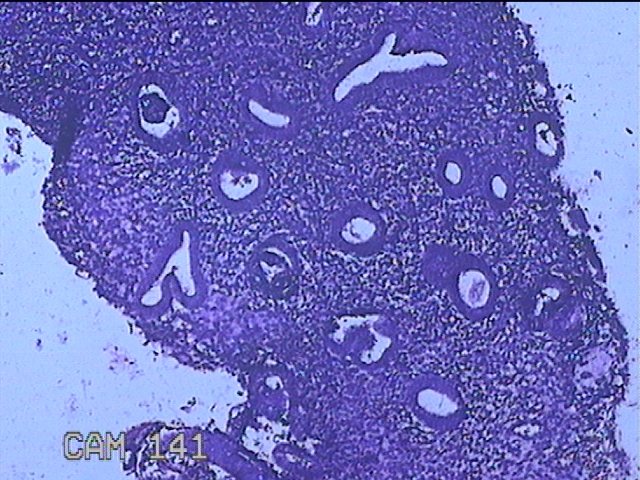

性别

女

年龄

36岁

临床诊断

子宫内膜炎

一般病史

经期延长1月。

标本名称

子宫腔内膜

大体所见

灰白暗红色不规则碎组织2.5x2.3x0.7cm一堆。

图1